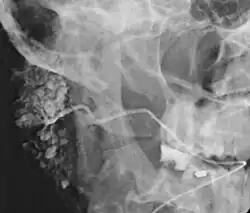

Die Sonografie kann die Diagnose in unklaren Fällen stützen. Die Sialografie kann bei chronischen Verläufen wertvolle Hinweise zur Differentialdiagnose geben. Bei einer chronisch-rezidivierenden Sialadenitis findet sich ein Bild wie bei einem „belaubten Baum“. Dagegen sind viele Drüsengänge bei einem Sjögren-Syndrom zerstört („rarefiziert“), sodass sich das Bild eines „entlaubten Baumes“ ergibt. Bei einer akuten Speicheldrüsenentzündung ist die Sialografie kontraindiziert.